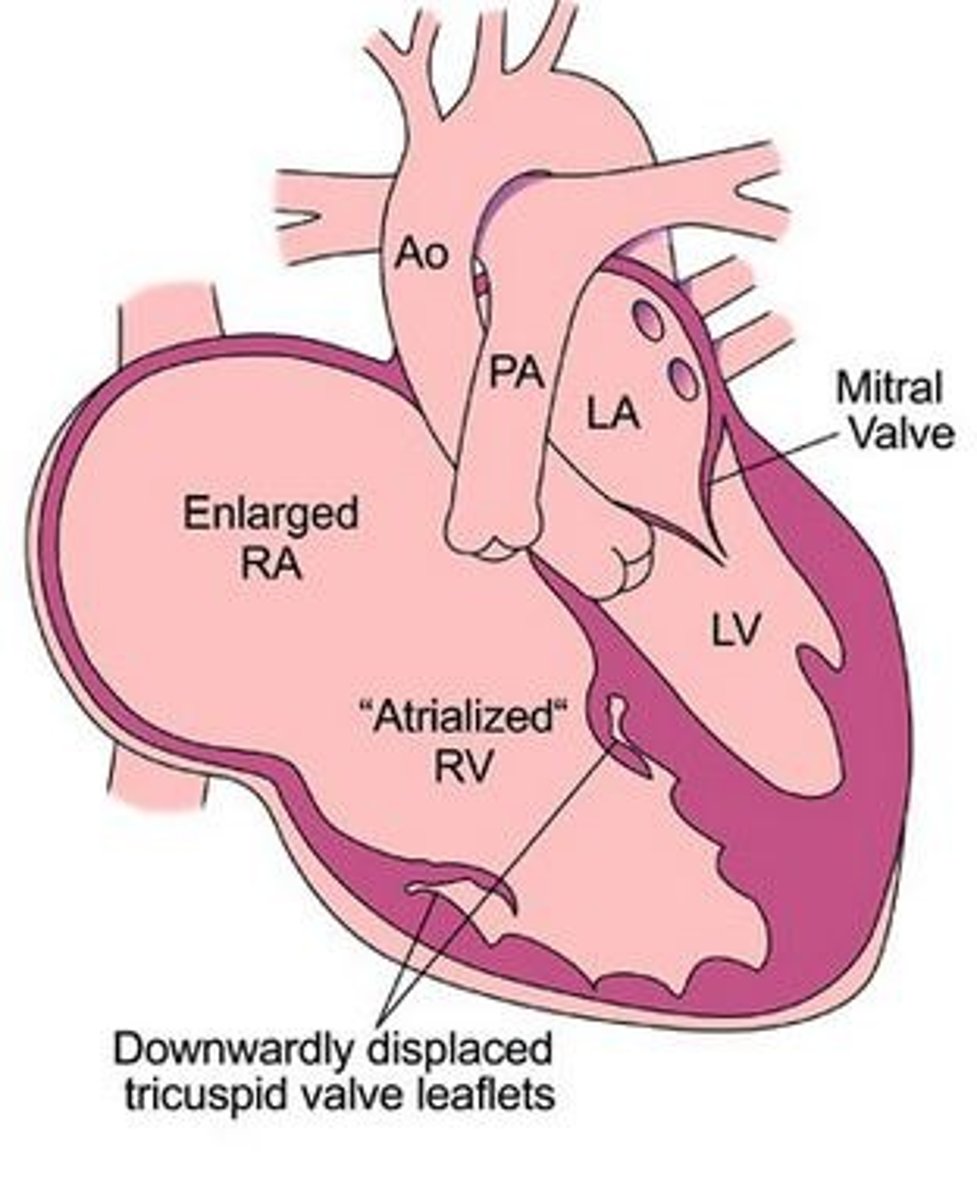

What congenital heart defect is associated with maternal lithium ingestion?

Ebstein anomaly